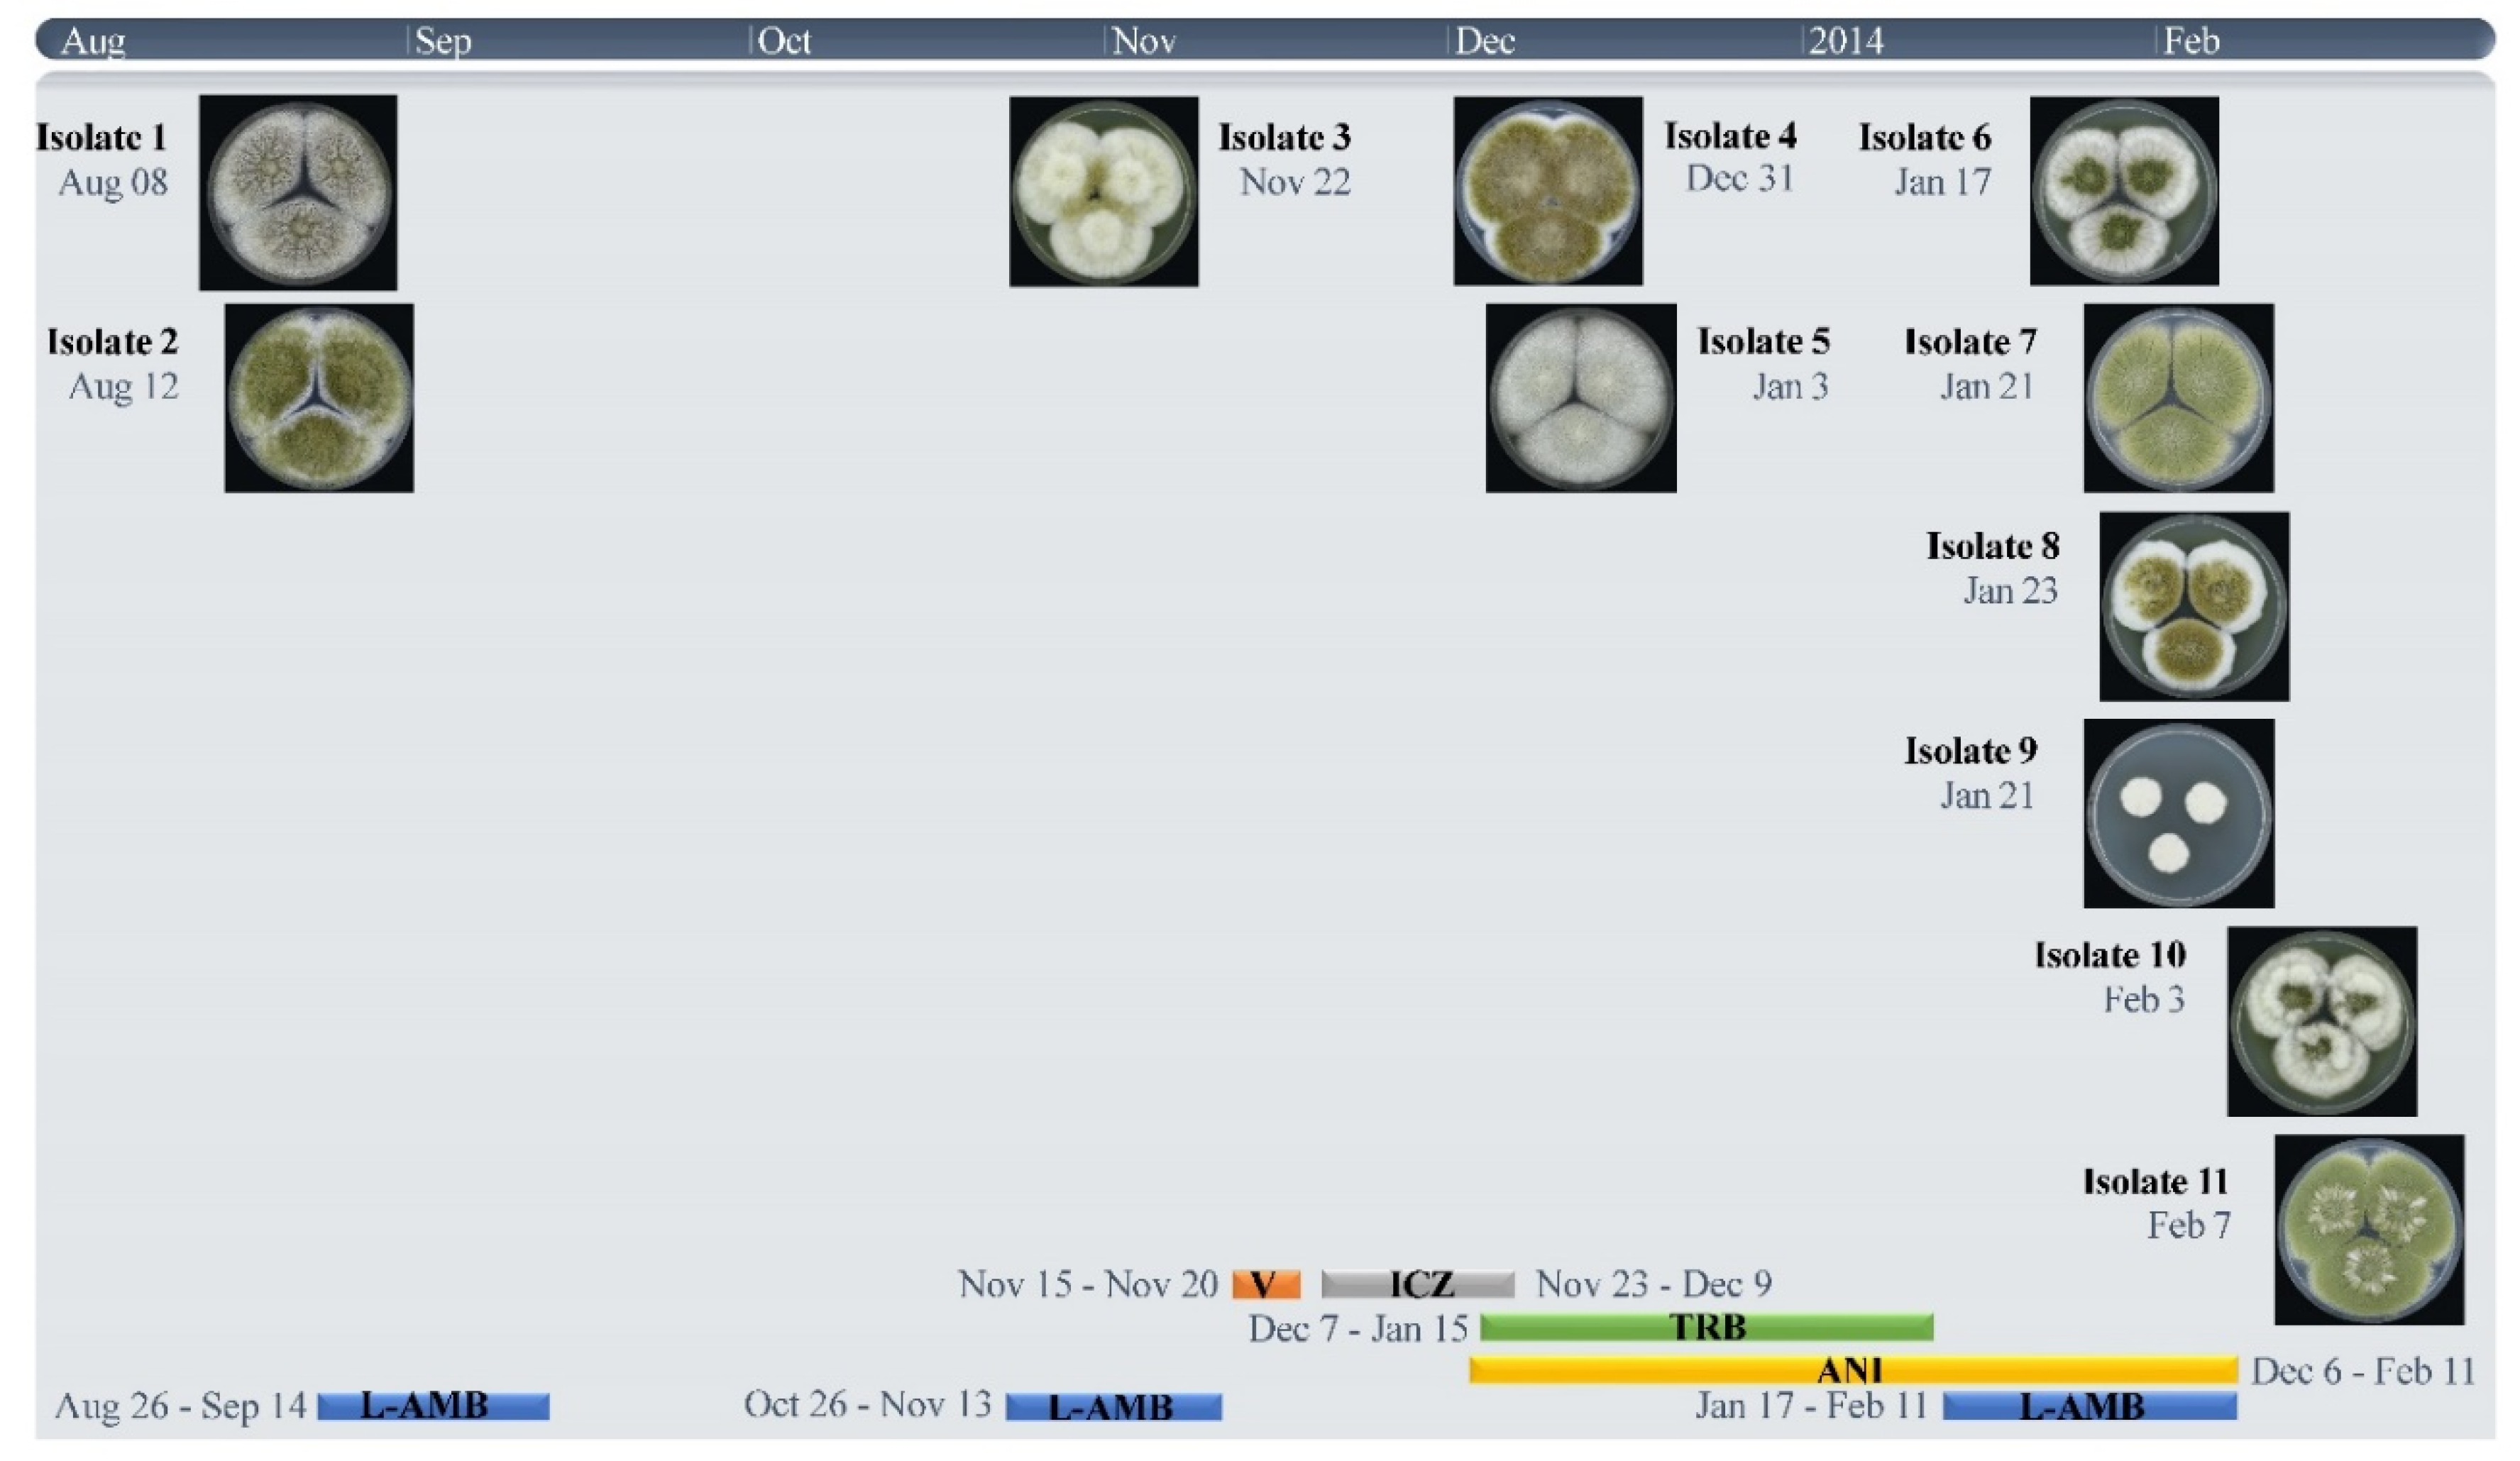

2.1. Origin of Strains and Antifungal Treatment

3.1. Strains, Phenotypical Analysis and Genotyping

| Strain Number | Isolation Date | MIC (mg/L) | STR Numbers | ||||||

|---|---|---|---|---|---|---|---|---|---|

| ITC | VOR | POSA | AMB | ANI c | 2 | 3 | 4 | ||

| 1 V152-39 | 8-8-2013 | 0.5 | 1 | 0.5 | 1 | 0.063 | 23-14-17 | 8-22-12 | 5-7-2011 |

| 2 V152-49 | 12-8-2013 | 1 | 4 | 0.25 | 2 | 0.031 | 23-14-17 | 8-22-12 | 5-7-2011 |

| 3 V156-58 | 22-11-2013 | 16 a | >16 | 0.5 | 2 | 0.031 | 23-14-17 | 8-22-12 | 5-7-2011 |

| 4 V158-11 | 31-12-2013 | >16 a,b | >16 b | 1 | 2 | 0.063 | 23-14-17 | 8-22-12 | 5-7-2011 |

| 5 V158-20 | 3-1-2014 | 16 a | 16 | 0.5 | 1 | 0.016 | 23-14-17 | 8-22-12 | 5-7-2011 |

| 6 V158-70 | 17-1-2014 | 2 | >16 | 0.5 | 2 | 0.016 | 23-14-17 | 8-22-12 | 5-7-2011 |

| 7 V158-75 | 21-1-2014 | >16 a | >16 | 1 | 2 | 0.125 | 23-14-17 | 8-22-12 | 5-7-2011 |

| 8 V158-76 | 23-1-2014 | >16 a | >16 | 1 | 2 | 0.125 | 23-14-17 | 8-22-12 | 5-7-2011 |

| 9 V158-77 | 21-1-2014 | 1 | 16 | 0.25 | 2 | 0.25 | 23-14-17 | 8-22-12 | 5-7-2011 |

| 10 V159-40 | 3-2-2014 | >16 a | >16 | 2 | 2 | 0.031 | 23-14-17 | 8-22-12 | 5-7-2011 |

| 11 V159-56 | 7-2-2014 | 1 | >16 | 0.5 | 2 | 0.016 | 24-14-17 | 8-22-12 | 5-7-2011 |